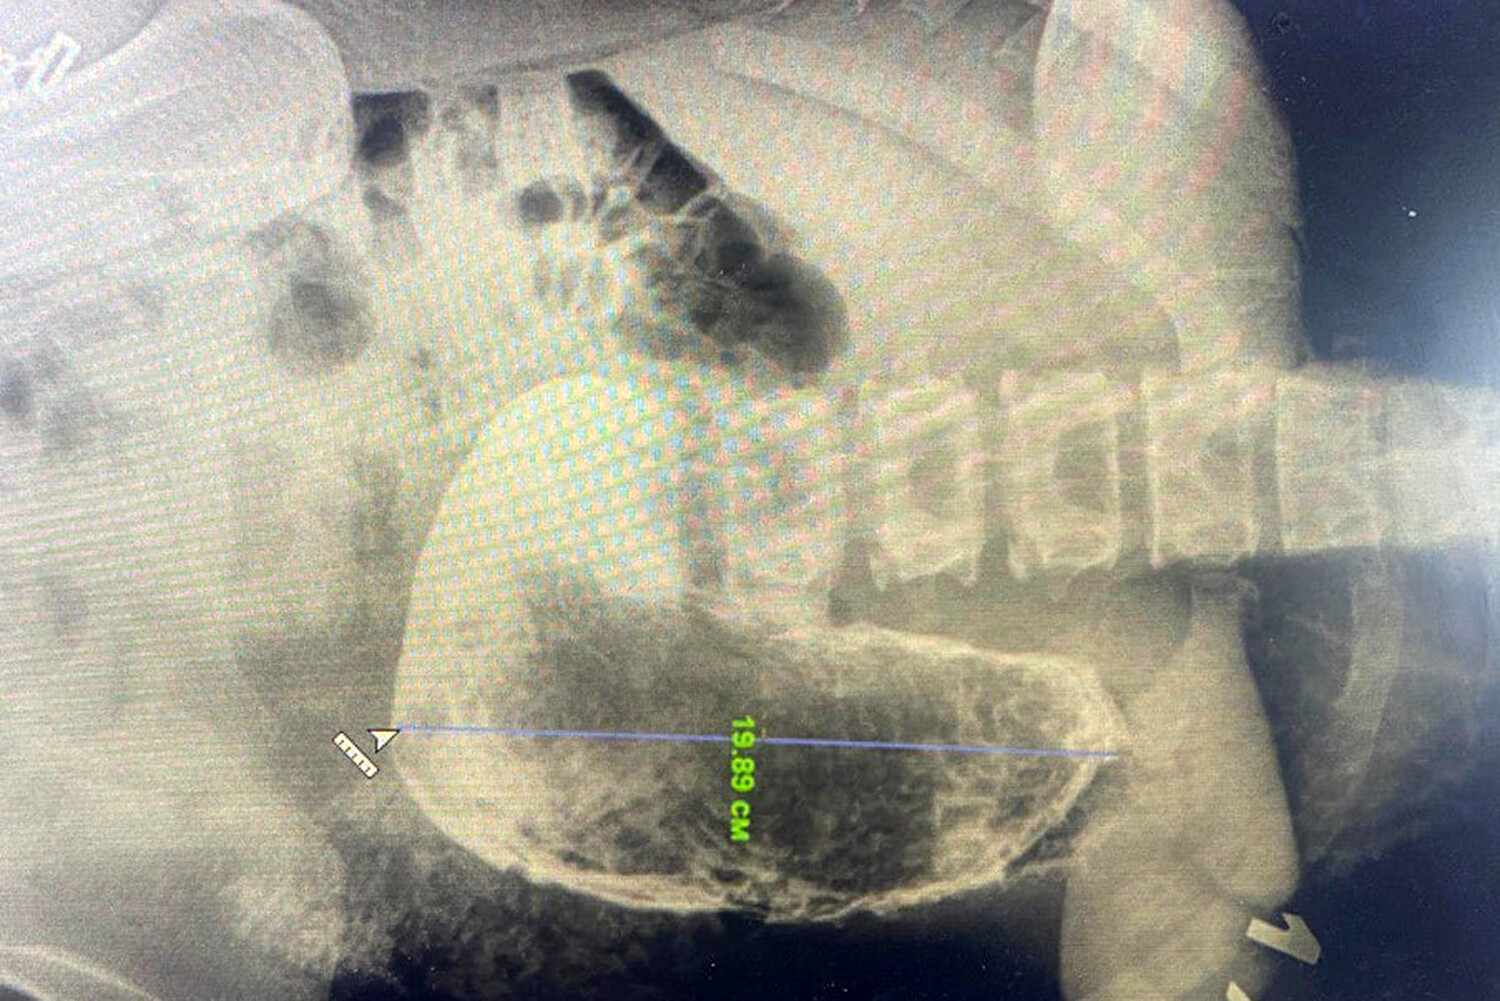

19-летняя девушка поступила в медицинское учреждение с жалобами на сильные боли в области живота, рвоту и тошноту. В ходе обследования врачи обнаружили в желудке пациентки инородное тело размером 20 см.

«Из-за больших размеров и плотной консистенции желудочного камня, мы приняли решение провести операцию, в ходе которой удалили образование через небольшой разрез. О составе безоара и причинах его возникновения более точно можно будет говорить, когда будут готовы результаты гистологического исследования», — рассказал заведующий хирургическим отделением Красногорской больницы Николай Мурашов.